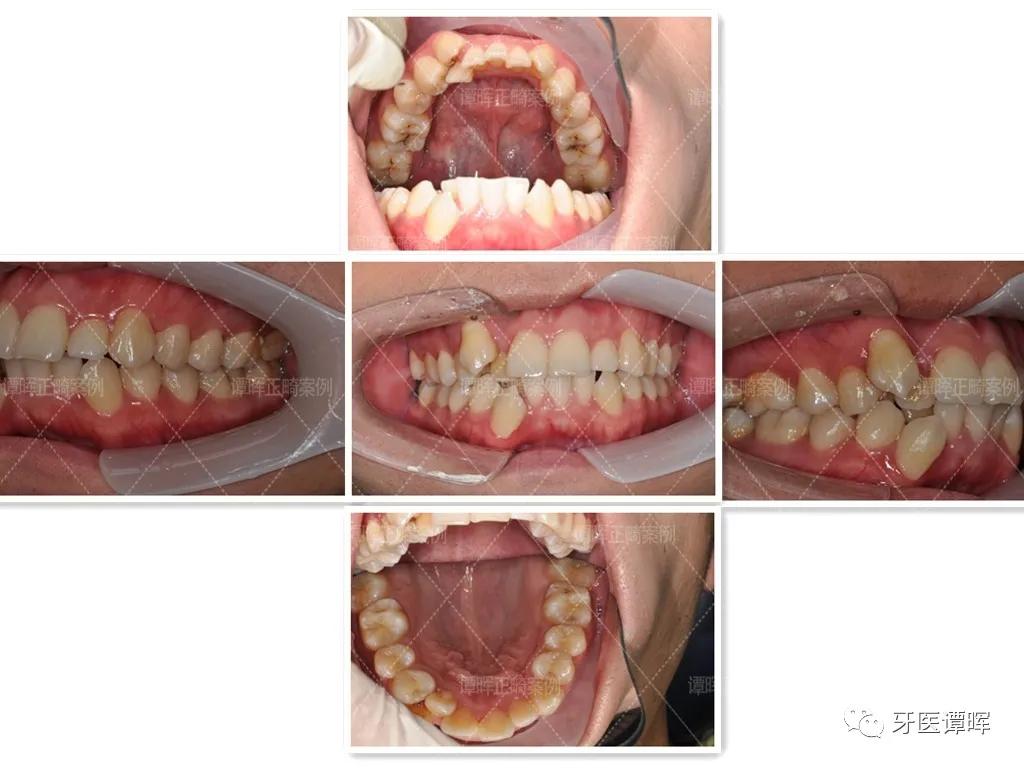

矫正前

矫正之前因牙齿拥挤使嘴巴看起来有点突,下门牙畸形错颌,没有办法正常咬食物,也因*牙虎**与另一颗牙重叠,吃东西时特别容易塞牙,因此牙周也不是很好。